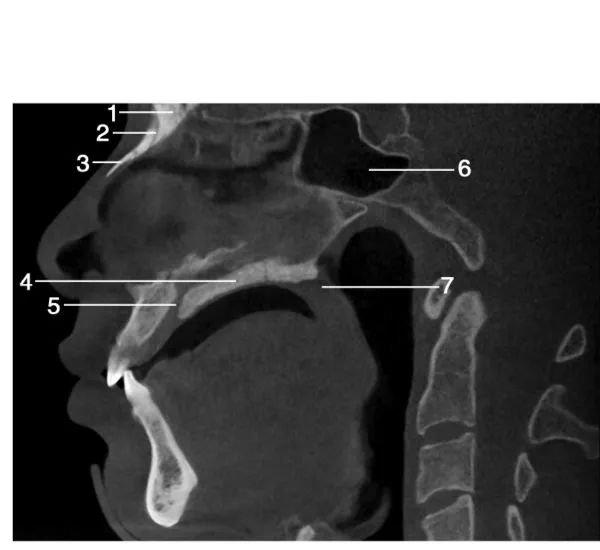

1.眶下裂( inferior orbital fissure) ; 2.眶下神经管( canal for infraorbital nerve) ; 3.上颌窦( maxillary sinus) ; 4.上颌窦前壁(anterior wall of maxillary sinus) ; 5.上颌第一磨牙( maxillary first molar) ; 6.眶底( floor of orbit) ; 7.上颌窦后壁( posterior wall of maxillary sinus) ; 8.翼突( pterygoid process) ; 9.上颌第三磨牙( maxillary third molar) ; 10.上颌第二磨牙( maxillary second molar)